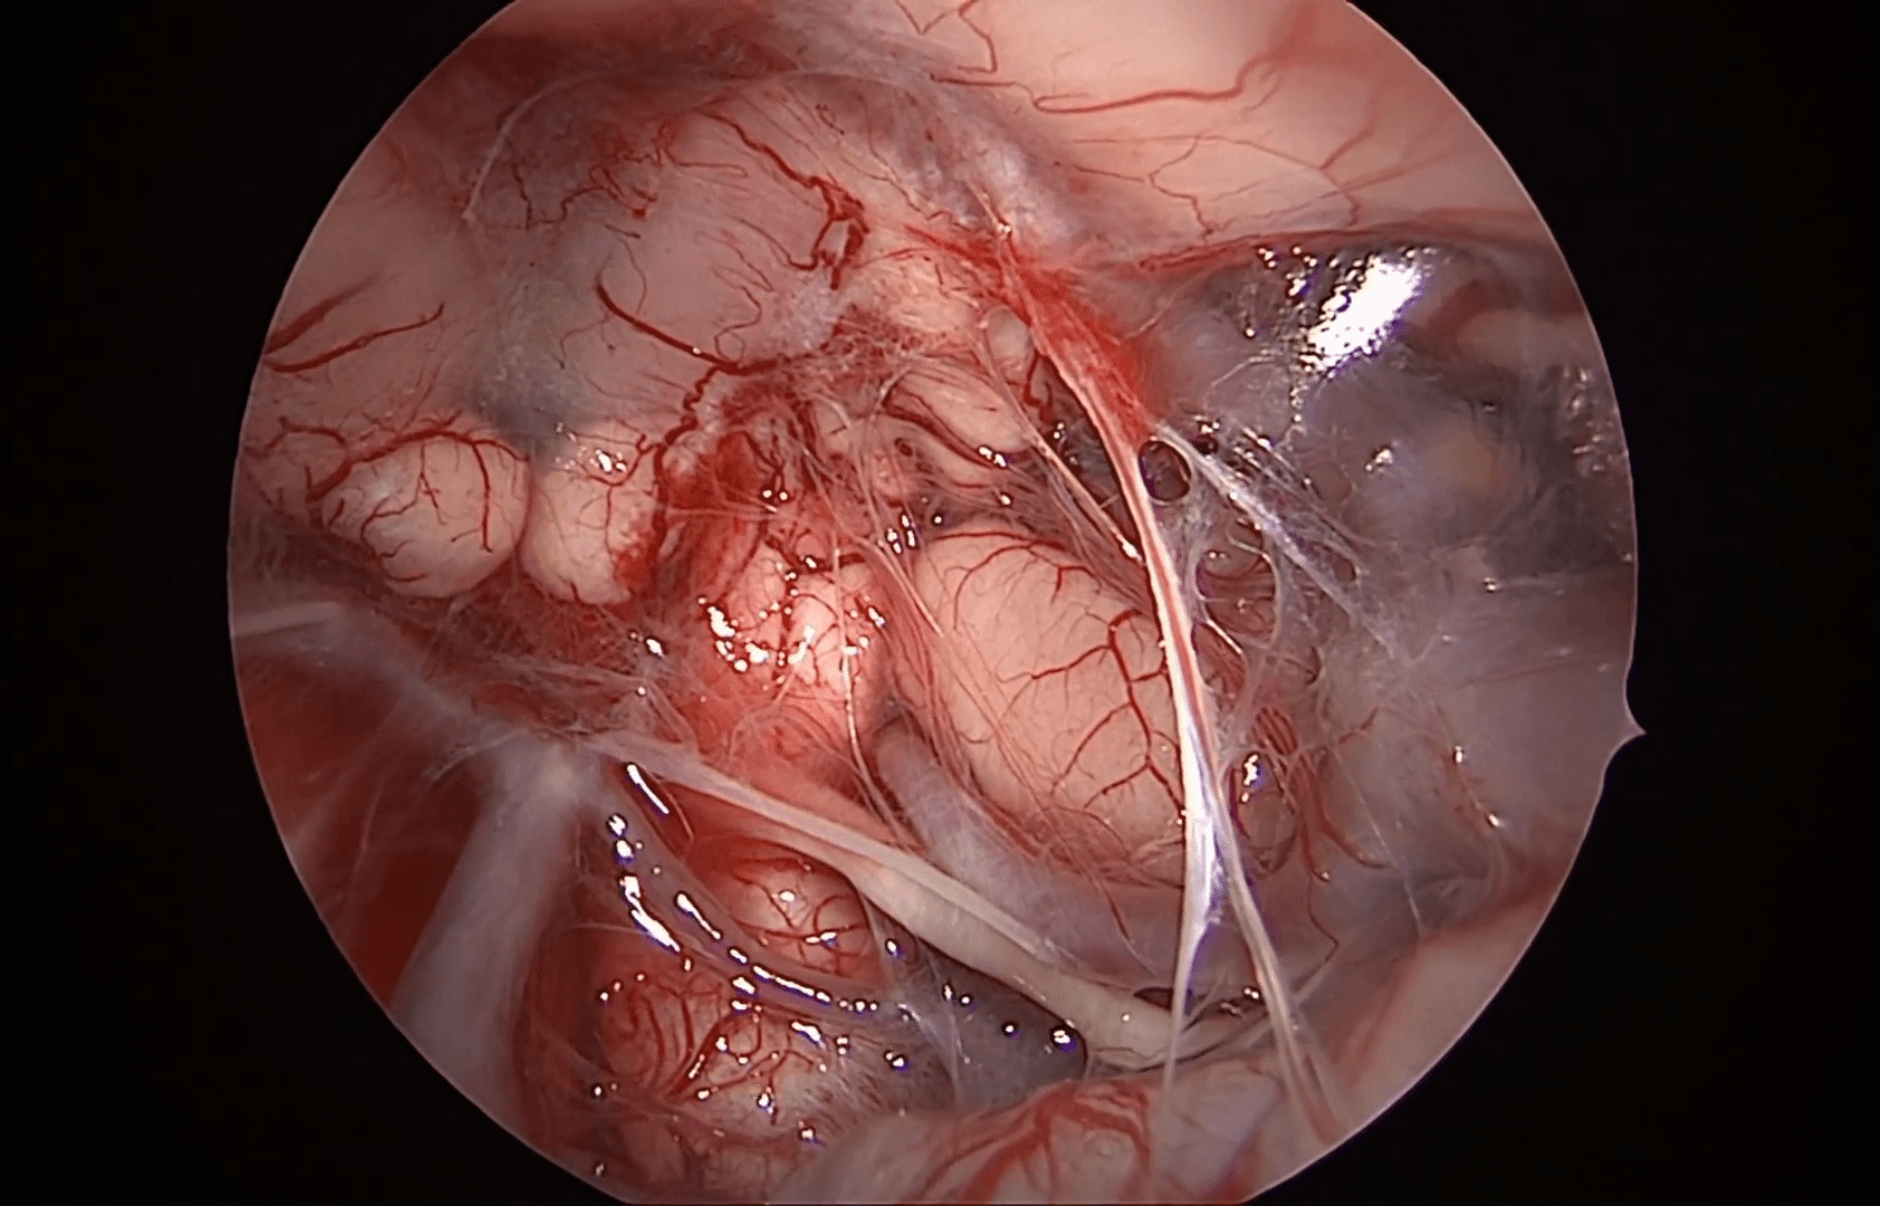

La fase transcavernosa es especialmente relevante en el condrosarcoma petroclival. El Dr. Rafael Martínez-Pérez diseca cuidadosamente el seno cavernoso medial, identificando la carótida interna y preservando las estructuras neurovasculares.

El trabajo en planos subperiósticos y la disección roma permiten minimizar el riesgo de lesión vascular. La movilización controlada de la carótida interna amplía el acceso lateral, facilitando la resección del componente tumoral más allá del eje medio.

La resección se lleva a cabo de forma progresiva, combinando aspiración, disección microquirúrgica y control constante de los límites anatómicos.

El abordaje transcavernoso implica enfrentarse a un entorno de alto riesgo vascular. El sangrado venoso del seno cavernoso puede comprometer la visibilidad quirúrgica si no se controla adecuadamente.

El Dr. Rafael Martínez-Pérez utiliza técnicas de hemostasia local con agentes hemostáticos y presión dirigida, evitando maniobras agresivas. El uso de Doppler intraoperatorio y navegación permite confirmar en todo momento la localización de la carótida interna.

Las ópticas anguladas juegan un papel fundamental, permitiendo la inspección de recesos y cavidades residuales. El Dr. Rafael Martínez-Pérez demuestra cómo la endoscopia avanzada mejora el control visual en áreas de difícil acceso.